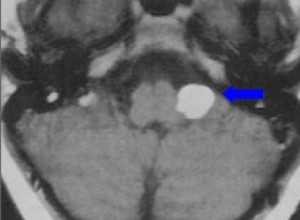

МРТ головного мозга. На мрт в аксиальной плоскости отмечается объемное образование внутреннего слухового прохода слева (стрелка), с четкими и неровными контурами, деформирующее окружающие структуры. После внутривенного введения парамагнитного контрастного вещества отмечается интенсивное и неоднородное его накопление образованием (изображение справа) — невринома.